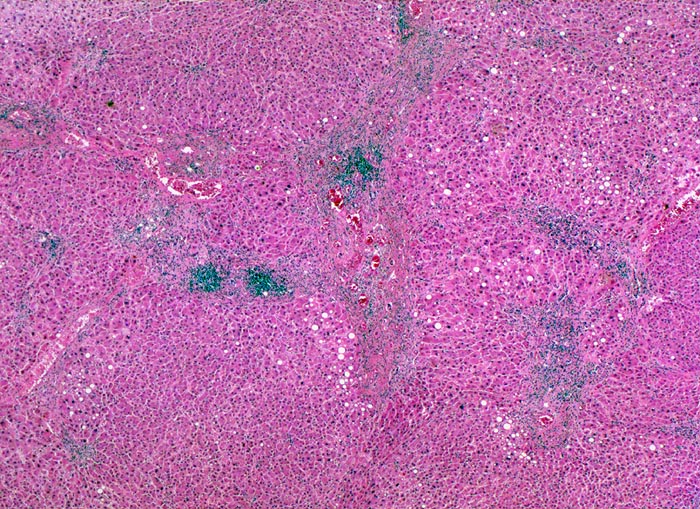

Makroskopisch imponiert das hepatozelluläre Karzinom als solitäre grosse Tumormasse, als zahlreiche zirrhoseartige Knoten oder als scharf begrenzter Knoten mit oder ohne Kapsel. Die tumorfreie Leber ist in der Mehrheit der Fälle zirrhotisch umgebaut. Mikroskopisch bilden die Tumorzellen mehr als 2 Zellen breite Trabekel (> 1237), kompakte Tumormassen (> 1229) oder pseudoglanduläre Strukturen (dilatierte Canaliculi) (> 1212) (> 1199). Desmoplastisches Bindegewebe fehlt meist. Innerhalb des Tumors fehlen Portalfelder. Es finden sich lediglich Arterien. Etwa bei der Hälfte der Karzinome lässt sich intrazytoplasmatische oder intracanaliculäre Galle (> 1238) nachweisen. Immunhistochemisch lassen sich mit einem polyklonalen Antikörper gegen Carcinoembryonales Antigen (CEA) Gallecanaliculi zwischen den Tumorzellen nachweisen. Die Tumorzellen bilden keinen Schleim.

• Die Tumorzellen bilden Trabekel, welche überwiegend mehr als 2 Zellen breit sind und Pseudodrüsen.

• Sinusoidartige Blutgefässe mit Endothelauskleidung verlaufen zwischen den Trabekeln und den Pseudodrüsen.

• Galle ist sichtbar in den Pseudodrüsen.

• Tumorfreies Parenchym mit chronischer viraler Hepatitis (B und D): dichtes chronisches Entzündungsinfiltrat in den Portalfeldern übergreifend auf das Parenchym (Interfacehepatitis). Spärliche intralobuläre Entzündung mit Einzelzellnekrosen (Apoptosen). Fibrose der Portalfelder mit Septenbildung und unvollständigem zirrhotischem Umbau.

Geringe gemischttropfige Verfettung des Leberparenchyms.